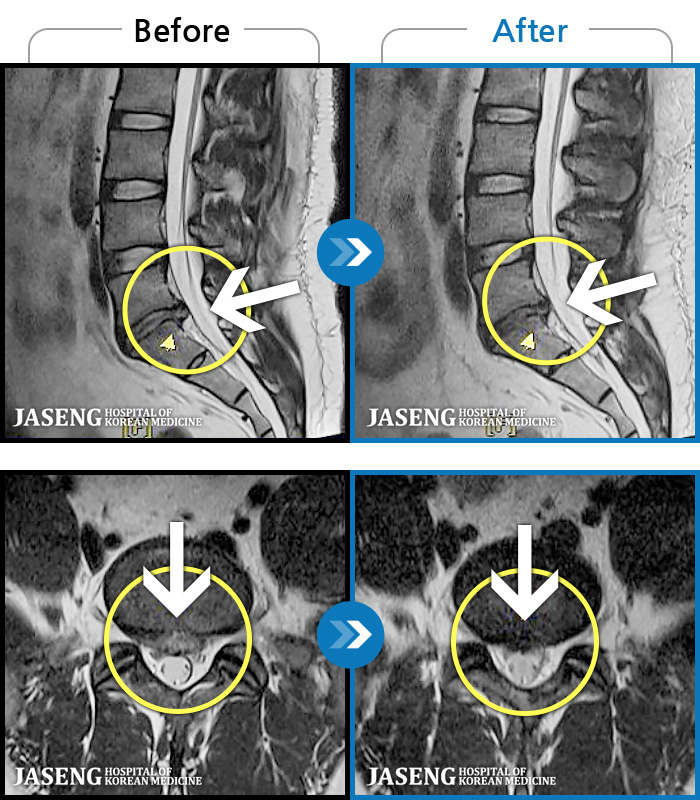

MRI ġ

1,301 MRI ũ ʸ Ȯϼ.